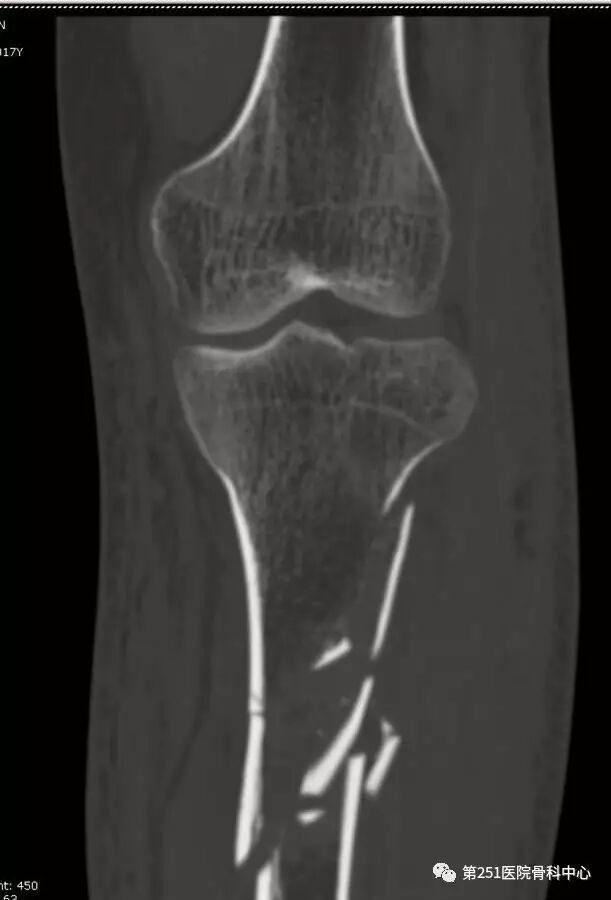

病例2:男性,44岁,车祸伤,双侧胫腓骨骨折(左侧)。